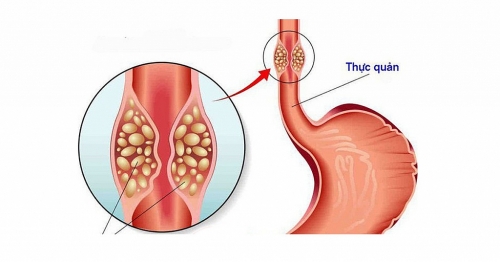

Dấu hiệu nhận biết ung thư thực quản

Ung thư thực quản là gì? Dấu hiệu nhận biết ung thư thực quản như thế nào? Hãy cùng tìm hiểu ngay sau đây: